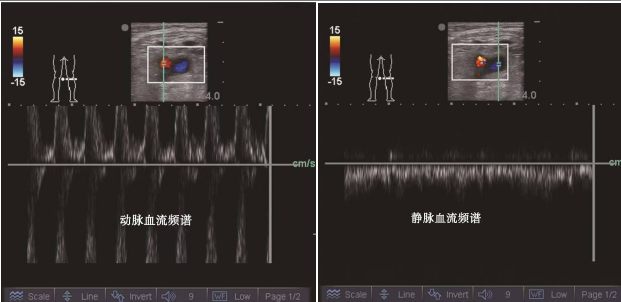

④脉冲多普勒法

找到目标血管后,打开超声的脉冲多普勒血流显像,将采样框放到相应的血管上,就可以看见相应血管的血流频谱,动脉血流呈规律搏动样高频信号,而静脉血流呈连续性低频信号。